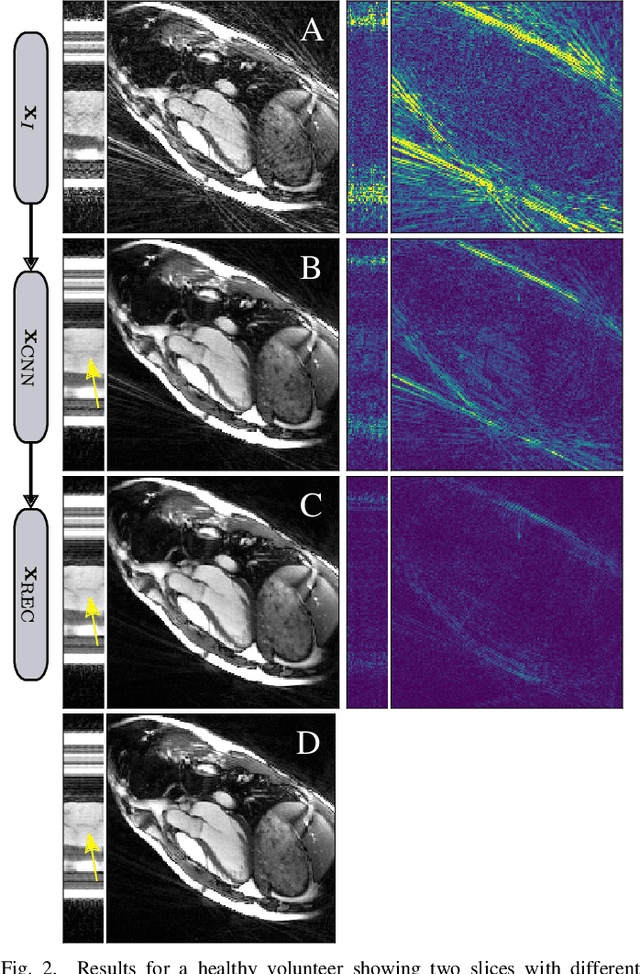

Abstract:Purpose: Iterative Convolutional Neural Networks (CNNs) which resemble unrolled learned iterative schemes have shown to consistently deliver state-of-the-art results for image reconstruction problems across different imaging modalities. However, because these methodes include the forward model in the architecture, their applicability is often restricted to either relatively small reconstruction problems or to problems with operators which are computationally cheap to compute. As a consequence, they have so far not been applied to dynamic non-Cartesian multi-coil reconstruction problems. Methods: In this work, we propose a CNN-architecture for image reconstruction of accelerated 2D radial cine MRI with multiple receiver coils. The network is based on a computationally light CNN-component and a subsequent conjugate gradient (CG) method which can be jointly trained end-to-end using an efficient training strategy. We investigate the proposed training-strategy and compare our method to other well-known reconstruction techniques with learned and non-learned regularization methods. Results: Our proposed method outperforms all other methods based on non-learned regularization. Further, it performs similar or better than a CNN-based method employing a 3D U-Net and a method using adaptive dictionary learning. In addition, we empirically demonstrate that even by training the network with only iteration, it is possible to increase the length of the network at test time and further improve the results. Conclusions: End-to-end training allows to highly reduce the number of trainable parameters of and stabilize the reconstruction network. Further, because it is possible to change the length of the network at test time, the need to find a compromise between the complexity of the CNN-block and the number of iterations in each CG-block becomes irrelevant.

Abstract:In this work, we propose an iterative reconstruction scheme (ALONE - Adaptive Learning Of NEtworks) for 2D radial cine MRI based on ground truth-free unsupervised learning of shallow convolutional neural networks. The network is trained to approximate patches of the current estimate of the solution during the reconstruction. By imposing a shallow network topology and constraining the $L_2$-norm of the learned filters, the network's representation power is limited in order not to be able to recover noise. Therefore, the network can be interpreted to perform a low dimensional approximation of the patches for stabilizing the inversion process. We compare the proposed reconstruction scheme to two ground truth-free reconstruction methods, namely a well known Total Variation (TV) minimization and an unsupervised adaptive Dictionary Learning (DIC) method. The proposed method outperforms both methods with respect to all reported quantitative measures. Further, in contrast to DIC, where the sparse approximation of the patches involves the solution of a complex optimization problem, ALONE only requires a forward pass of all patches through the shallow network and therefore significantly accelerates the reconstruction.